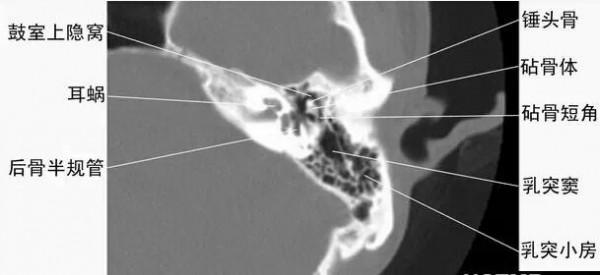

2耳部橫斷面-CT - 解剖圖片